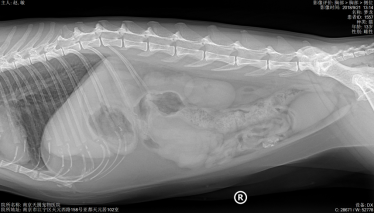

X光显示肺纹理增粗,其他未见异常。

经过5天住院治疗,住院期间患猫少量进食,未见呕吐、腹泻,多尿,水和良好,但仍有腹痛感。复查CBC,提示炎症未见下降;基础生化,提示应激;胸腔X线片,未出现转移情况,建议手术切除肿物送检。